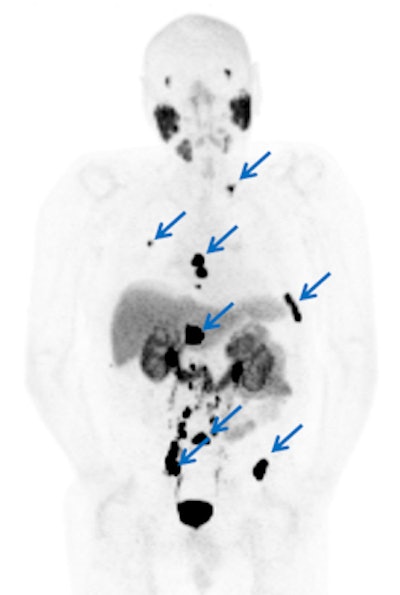

The researchers found "rapid" and "very high" accumulation of DCFPyL in putative foci of prostate cancer, with some lesions demonstrating maximum standardized uptake values (SUVmax) greater than 100.

The low blood-pool activity of DCFPyL also allowed for higher lesion conspicuity compared to DCFBC, they wrote.